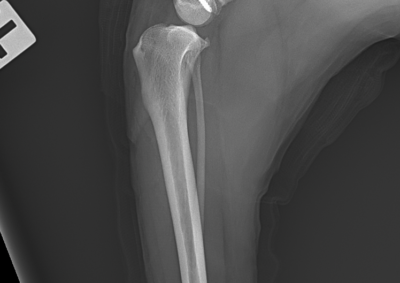

注意 ボタンをクリックした先に、治療中および手術中の画像が説明で使用されている場合がございます。 そのような画像に弱い方は閲覧なさらないようお願いいたします。 整形外科 若齢犬の橈骨固定術 #271 整形外科 前十字靭帯断裂(中型犬)に対するCBLO #255 整形外科 超小型犬に対する上腕骨遠位Y字骨折 整形外科 大型犬の前十字靭帯疾患(慢性経過)に対するCBLO #254 整形外科 橈骨固定術 #270 整形外科 膝蓋骨内方脱臼に対する人工滑車置換術 PGR #23 整形外科 犬の前十字靭帯(疾患)部分断裂に対するCBLO #253 整形外科 犬の前十字靭帯断裂に対するCBLO #252 整形外科 膝蓋骨内方脱臼+前十字靭帯断裂に対するPGR#22・LSS 整形外科 大腿骨骨折 整形外科 橈骨固定術 #269 整形外科 上腕骨外顆骨折の癒合不全 123456> 症例カテゴリー 放射線治療整形外科軟部組織外科脳神経外科内科腫瘍外科救急・集中治療リハビリテーション科腫瘍内科内視鏡科脳神経科呼吸器外科中医・漢方猫の腎移植循環器科